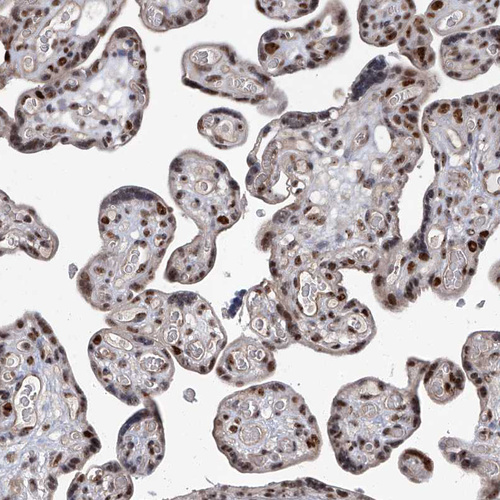

Immunohistochemistry analysis in human testis and liver tissues using HPA029979 antibody. Corresponding CMTR1 RNA-seq data are presented for the same tissues.